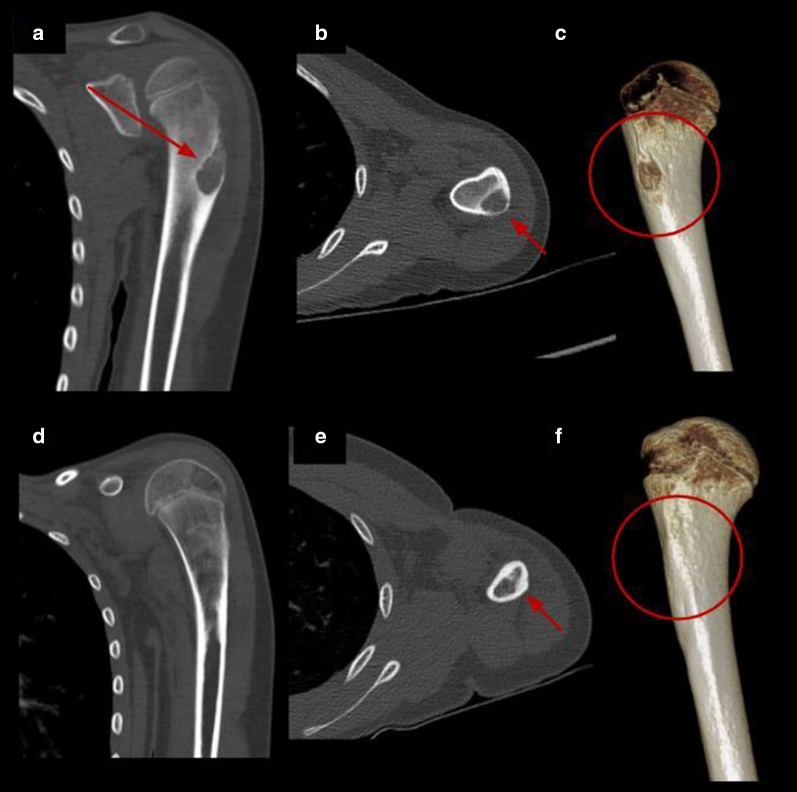

Fig. 4.

Percutaneous cryoablation of humeral osteoblastoma in a 9-y.o patient. a–c Coronal, axial CT images and volume rendering reconstruction of the left humerus show a lytic lesion consistent with osteoblastoma (red arrow and red circle). d–f Control CT 7 months after treatment with complete resolution of the lesion (red arrow and red circle)